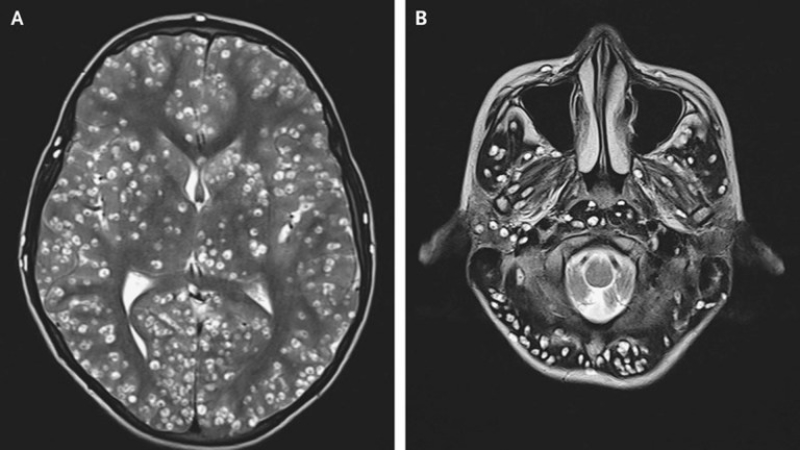

Cisticercos en el encéfalo